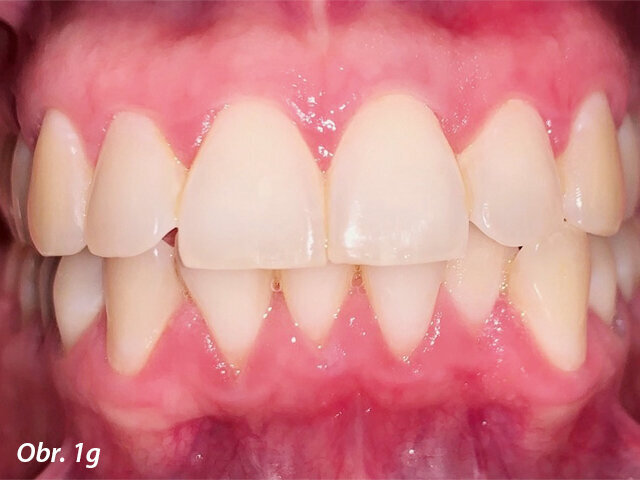

Pacientka 1 – Počáteční fotografie.